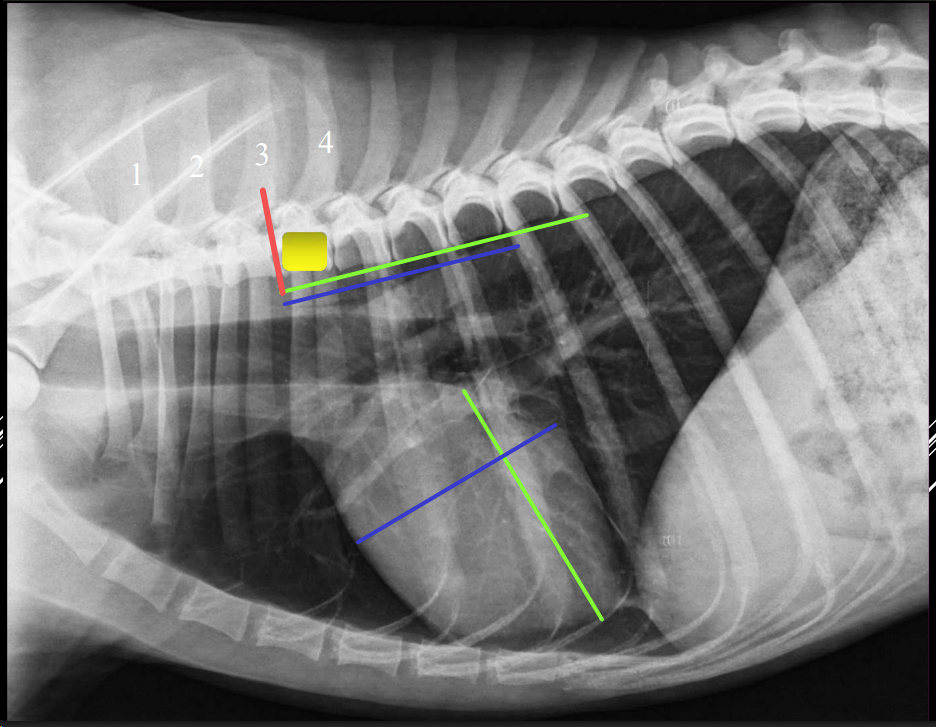

Índice de Buchanan (VHS):

- Eje A: bifurcación traqueal → ápex cardíaco.

- Eje B: perpendicular, medida craneocaudal.

- Referencia: 4ª vértebra torácica.

- Normalidad:

- Perro: 8,5–10,5

- Gato: <8,5